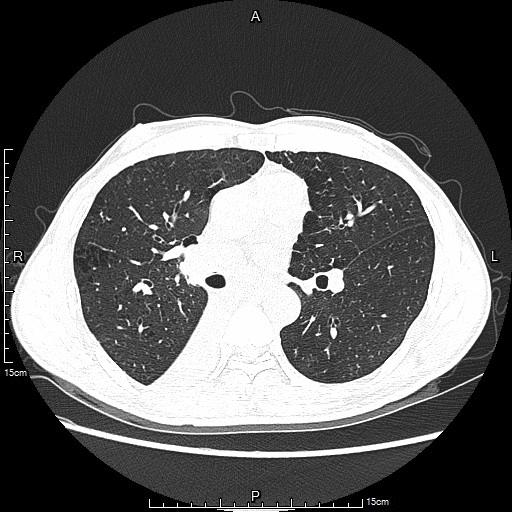

中年男性患者,诊断为右肺低分化鳞癌,经静脉化疗8周期静脉化疗,期间配合右肺门肿瘤放射性粒子植入,肿瘤仍未控进展。相关基因检测靶点无突变,无适合靶向药物治疗。胸部CT提示右下肺肿瘤进展并右下肺不张。

术前肺部CT(肺窗)

行DSA下支气管动脉化疗灌注治疗,术后1月复查肺部病灶明显缩小,右下肺大部分复张,相关临床症状亦明显改善。

术后1月肺部CT(肺窗)